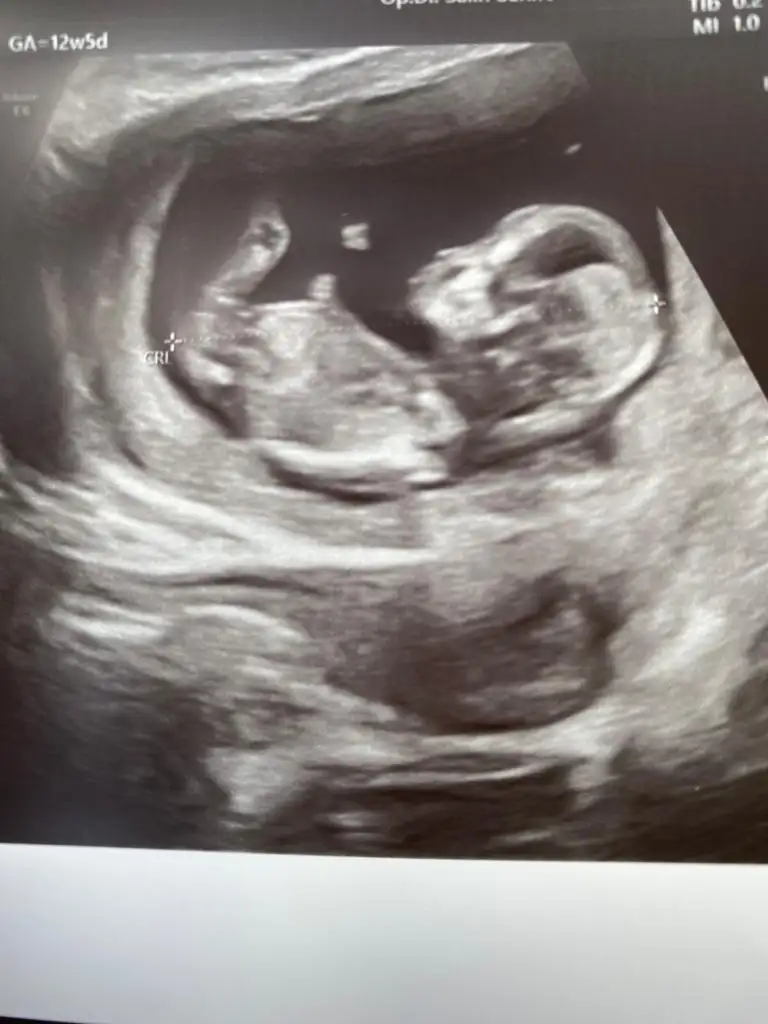

Kız gibi gibiTahmin istiyoruz 12+5